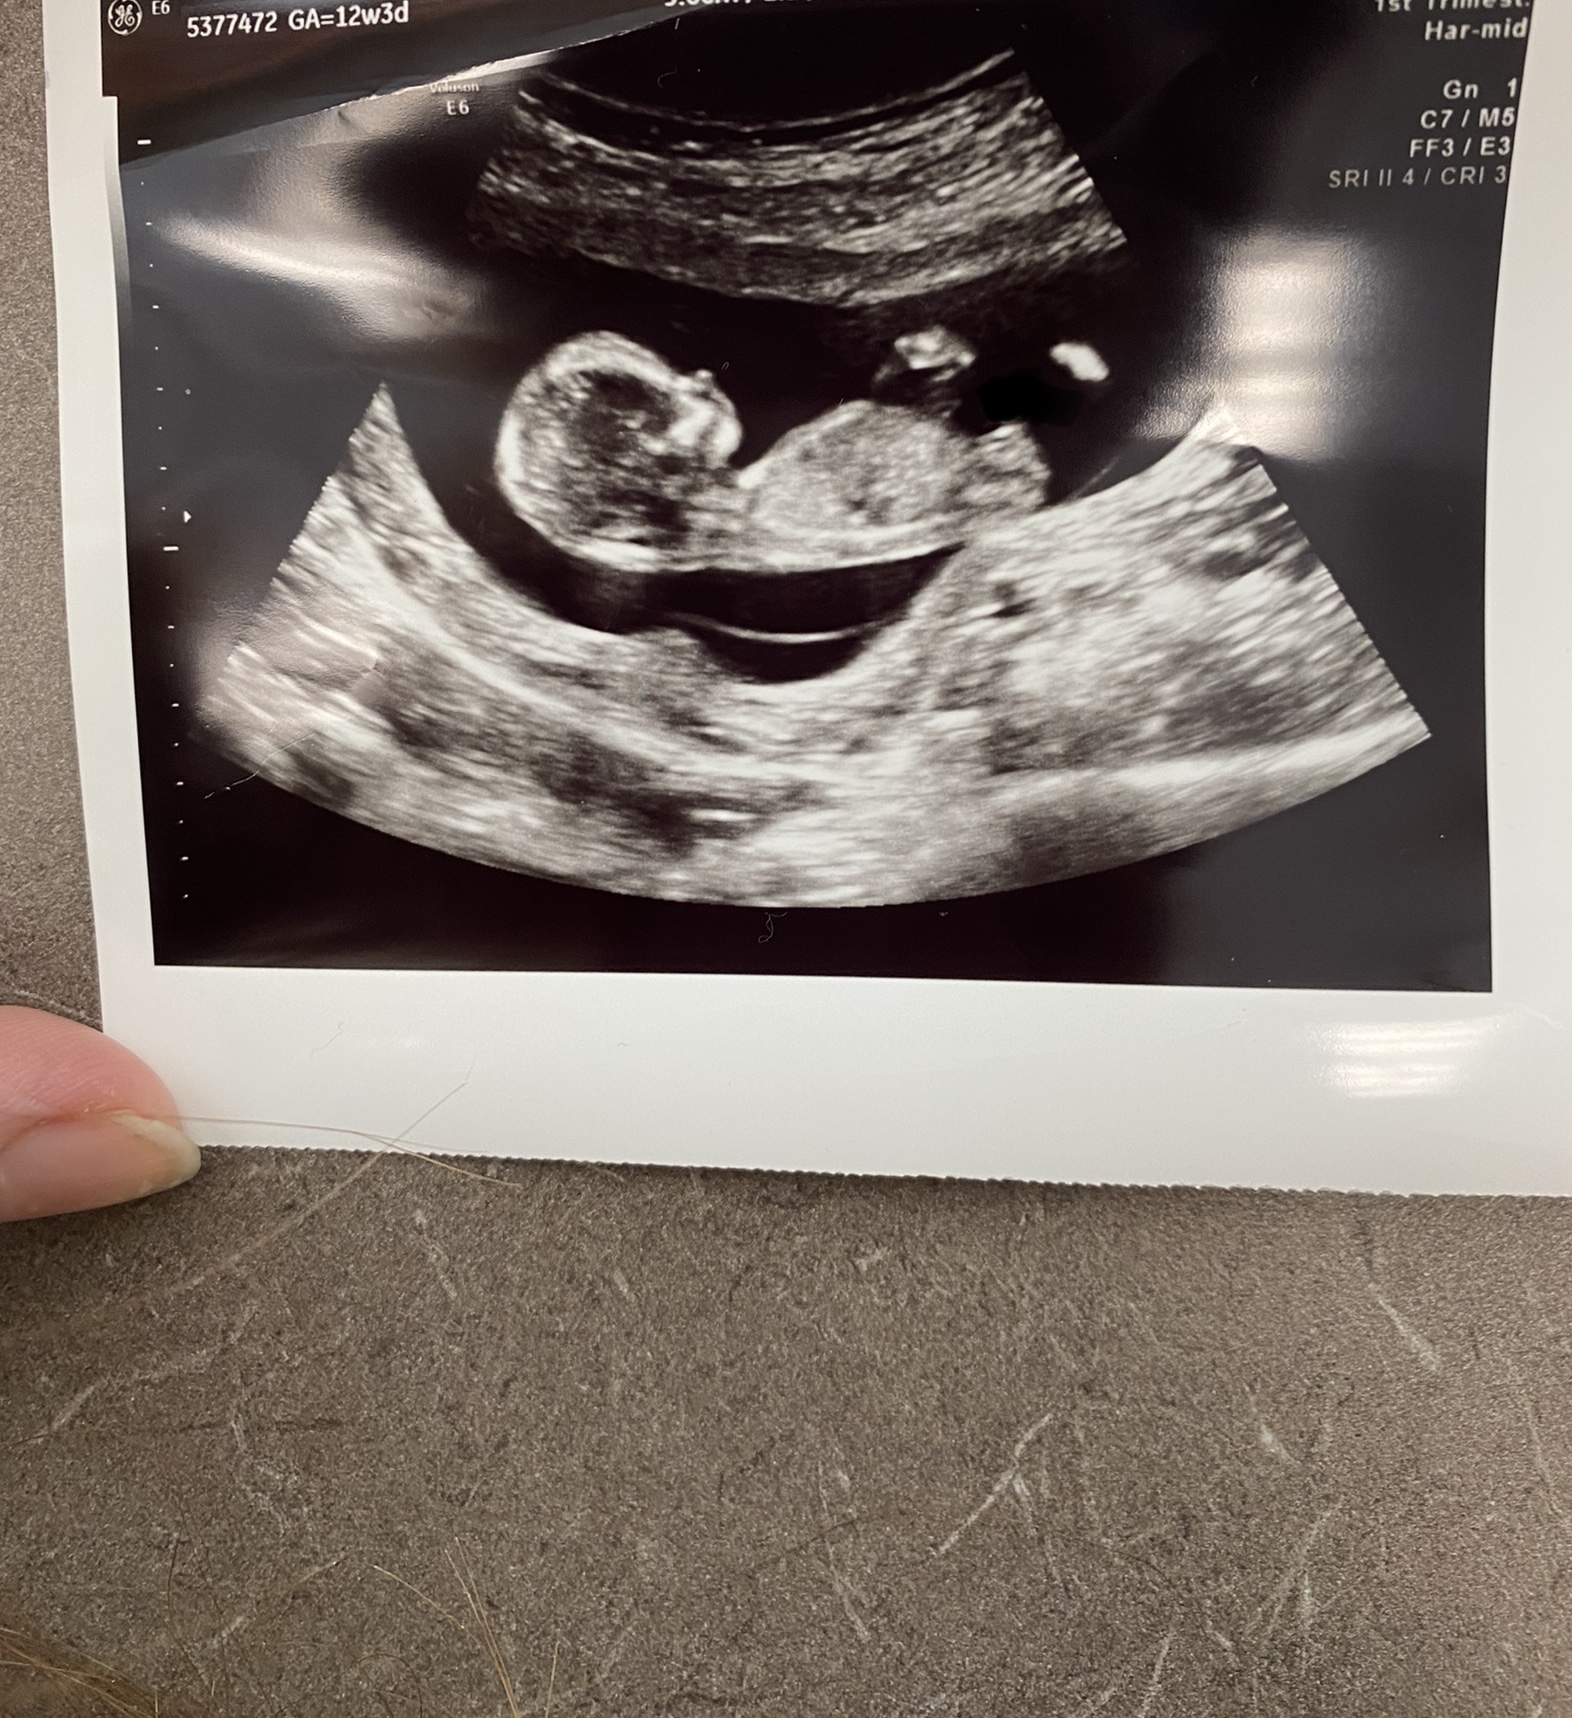

12 w 3 days really hoping for girl

I had my NT scan a few days ago baby kept moving a lot so my tech had a little hard time measuring. I didn’t see anything between legs I know it’s early. Only time I seen a nub on the screen and it looked like a fork then baby moved.

Cord was in way a lot.